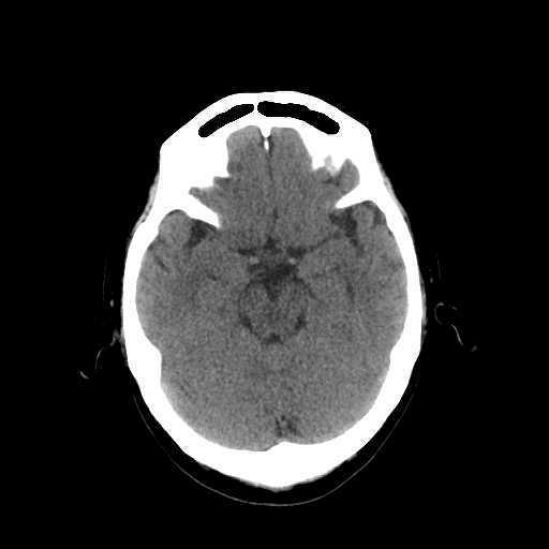

El Dr. López Tapia comentó que, lamentablemente, hoy en día 70% de quienes presentan alta sospecha de infarto cerebral llegan al hospital tarde y por sus propios medios y, ya estando ahí, resulta que el centro de salud no cuenta con un tomógrafo para el diagnóstico preciso, con terapia de reperfusión ni personal capacitado para suministrarla. “De modo que por cada minuto que pasa, el cerebro pierde cientos de neuronas, dejando al paciente con secuelas graves que se traducen en pérdida de la movilidad, visión, lenguaje y disminución de la capacidad intelectual[4]”.